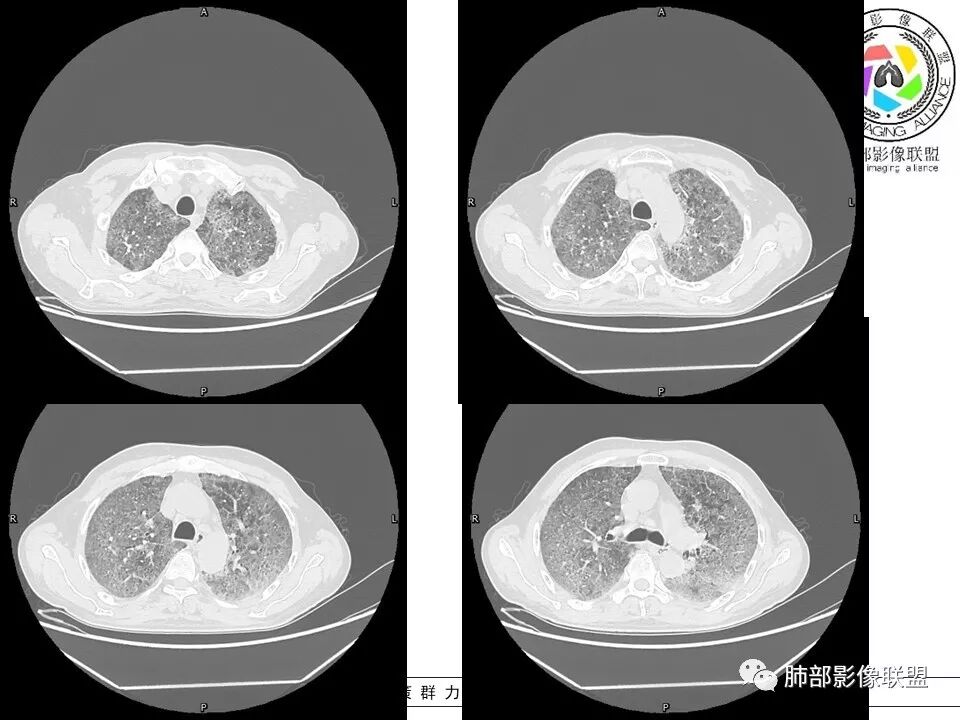

八爪:弥漫分布磨玻璃密度影,小叶间隔增厚,典型铺路石征,考虑PAP伴发感染性病变,鉴别特发性间质性肺炎,弥漫性腺癌,建议支气管灌洗;左肺上叶舌段不规则团片状阴影,显示不清,密切随访

小谢:慢性病程,无发热,双肺弥漫性病变,GGO,铺路石征,首先考虑PAP,鉴别肺腺癌

一米阳光:中老年男性,病程长。双肺弥漫性ggo,小叶间隔明显增厚,铺路石样改变,考虑PAP,鉴别pcp。建议支气管镜检查并灌洗。病史有尘肺接触史,排除尘肺合并结核

郑氏刀刀:双肺弥漫性磨玻璃影,伴铺路石征,下叶为主,且见斑片实变影,白细胞高,结合执业史,尘肺,PAP伴感染,腺癌待排。

小赵:中老年男性患者。慢性病程,多次咳黄痰,治疗效果一般,反复发生。CT表现为双肺弥漫磨玻璃样改变,并呈细网格样铺路石状改变,上下肺无明显差异。双下肺为主多发渗出实变,边界不清,抗炎治疗后病变吸收不明显,局部似有进展。考虑肺泡蛋白沉积症基础上合并感染。肿瘤标志物高,中老年患者,肺炎型肺癌不除外。

1、GGO+网格——碎石路征

2、分布无特定位置,较随机

3、可有少许实变——部分与层厚有关

5、病灶较多时部分可见重力趋势

1.由于脂蛋白的沉积和占据,肺泡腔含气量减少,这是影像上较大范围“磨玻璃影”的基础。

2.由液体、细胞浸润和纤维组织造成的小叶间隔增厚是影像上多边形“铺路石征”的基础。

3.显眼的小叶间隔对病灶有阻挡作用是形成影像上“地图样改变”的基础。我们观察到的病灶与临近相对正常肺组织之间常常有比较清楚的分界。

这种表现颇具特征性。但有部分患者(1/4)仅有磨玻璃影而未显示小叶间隔增厚,这种情形我们很难将PAP列为第一诊断。